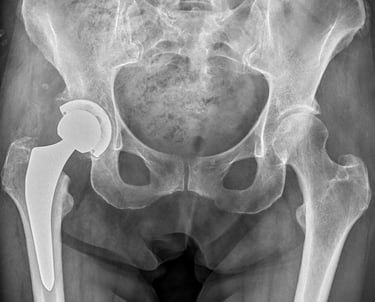

Chirurgia protesica d'anca

Impianti primari con tecnica mininvasiva ("HEROS approach")